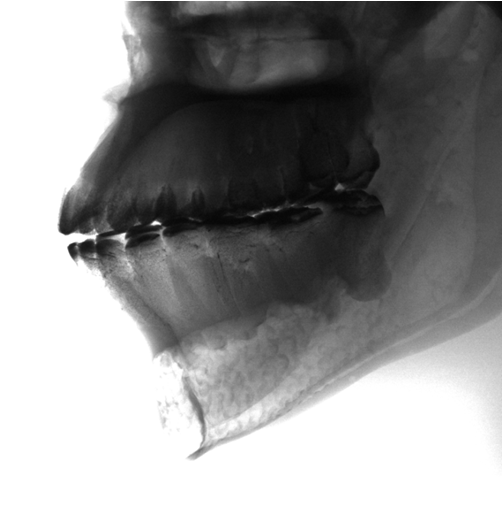

04.png